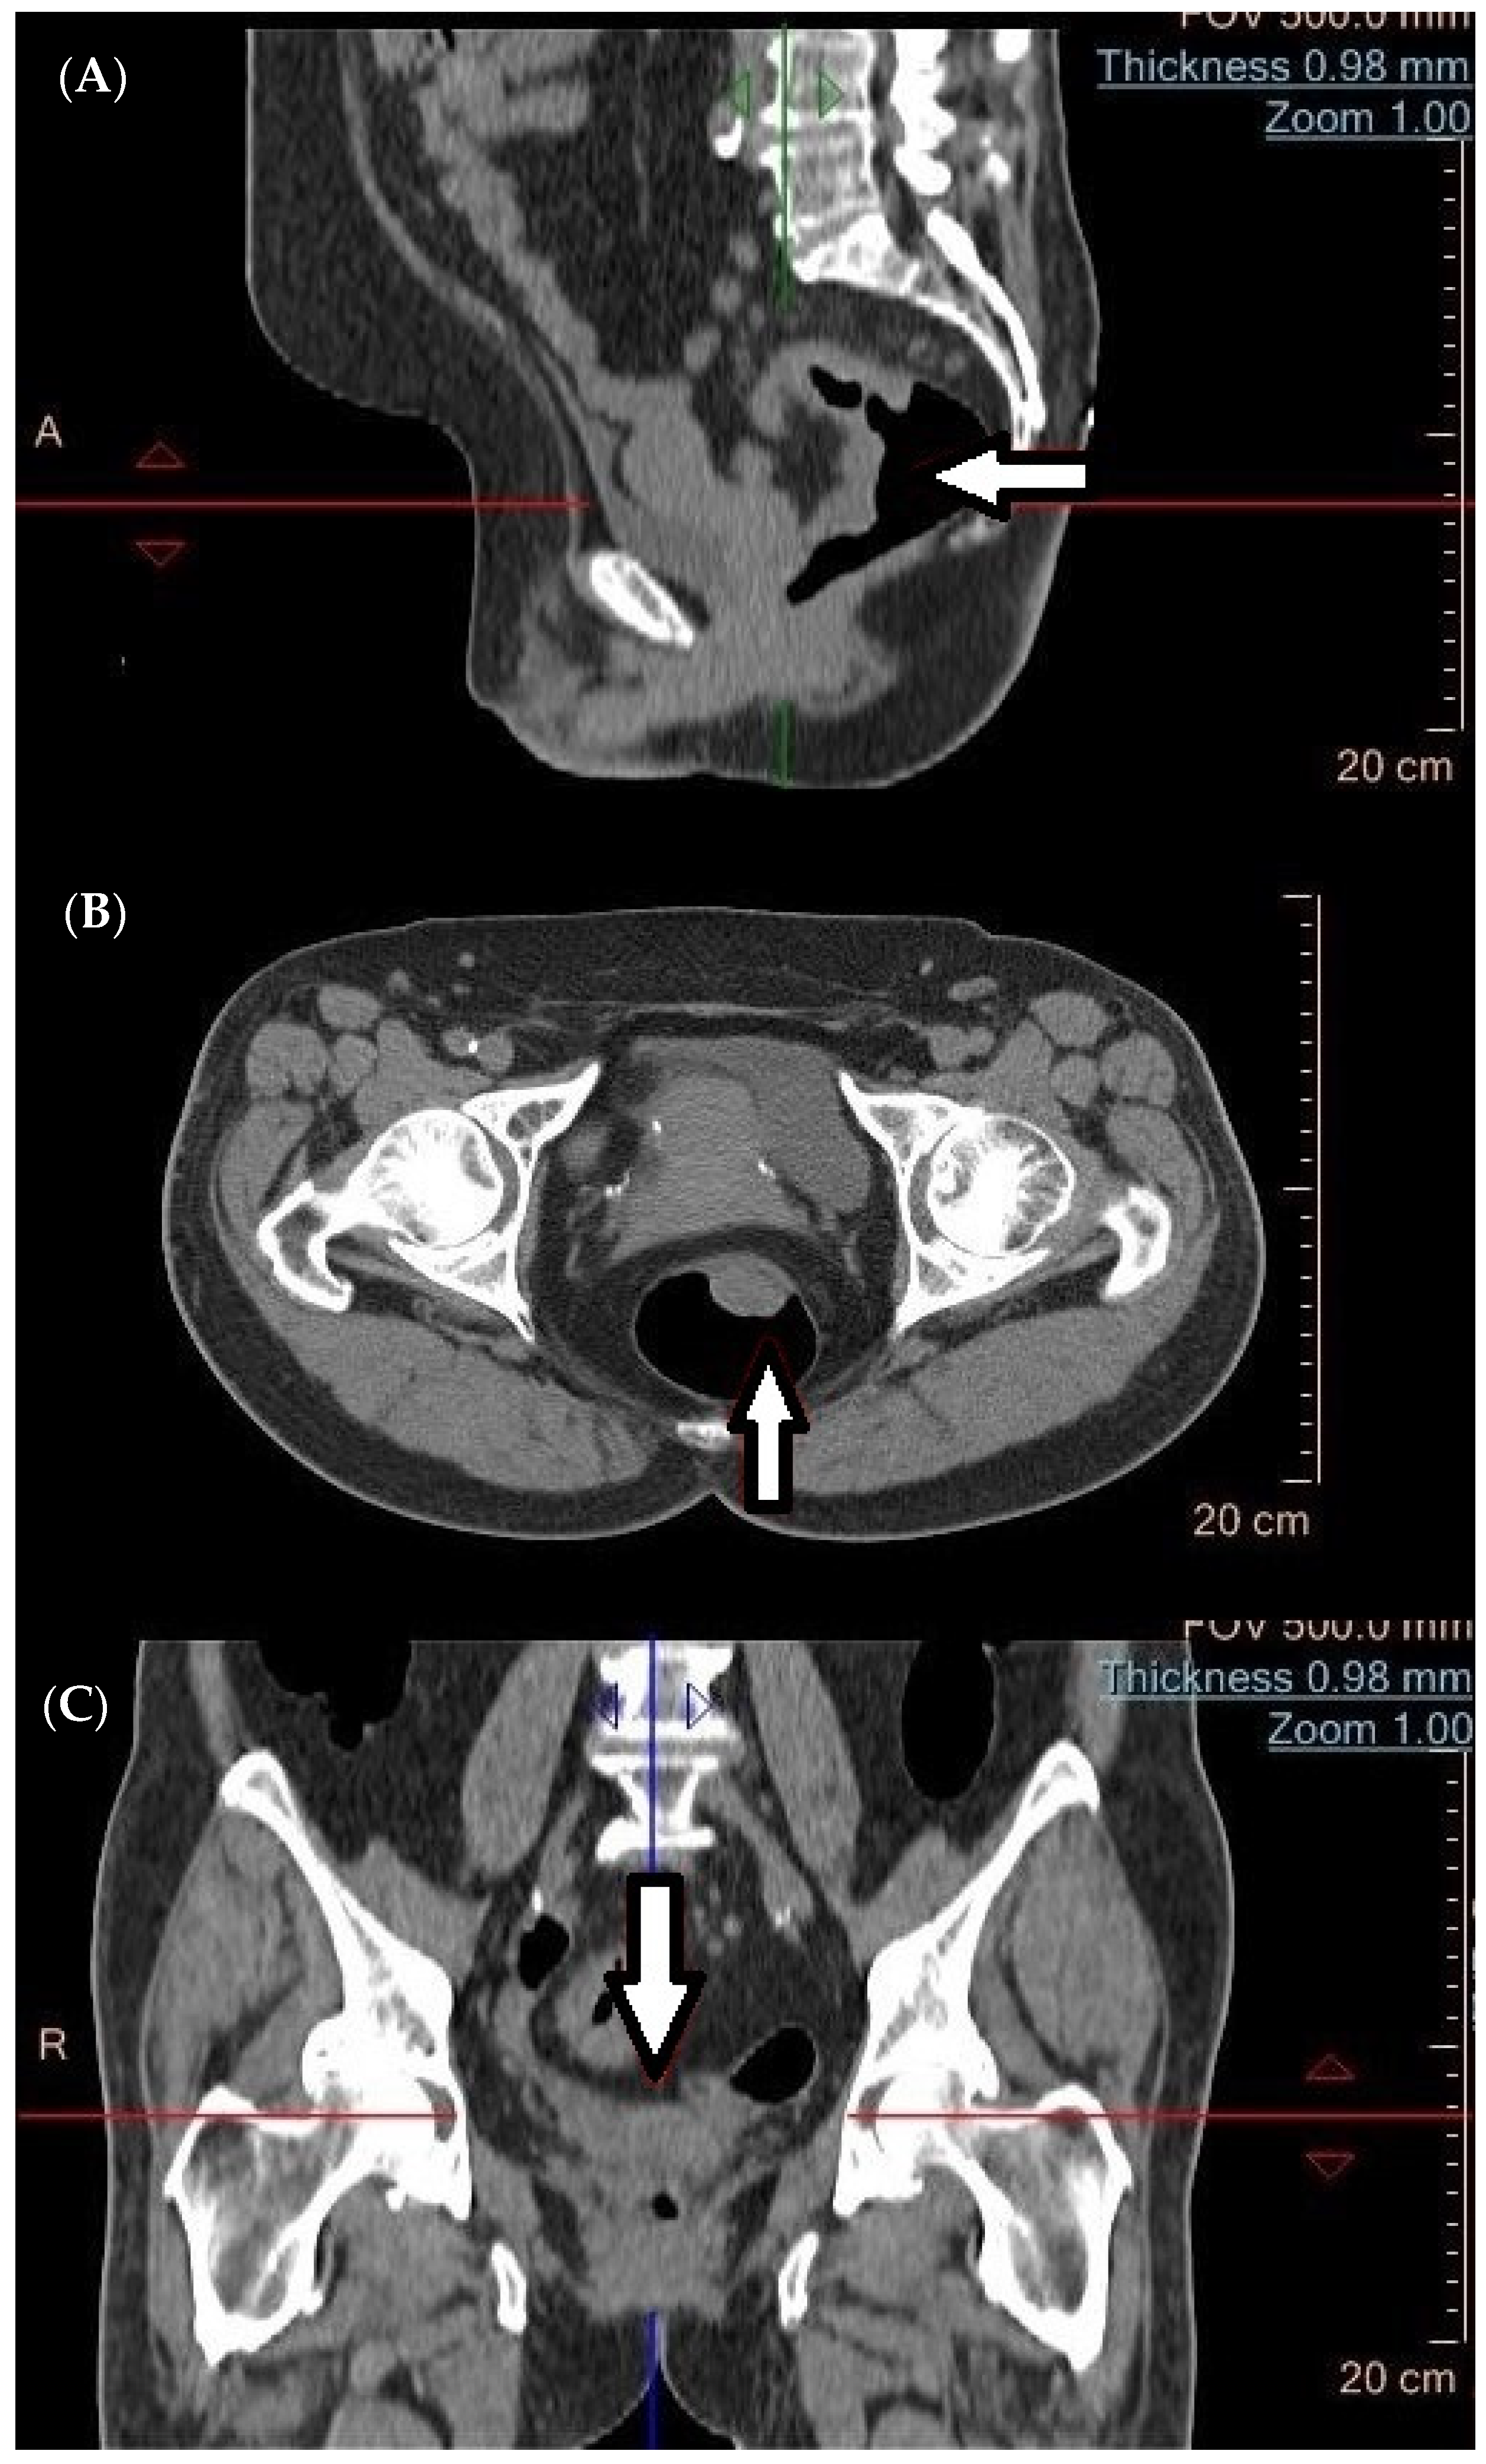

4. Computed Tomography (CT) in the Diagnosis of Metastatic Tumors